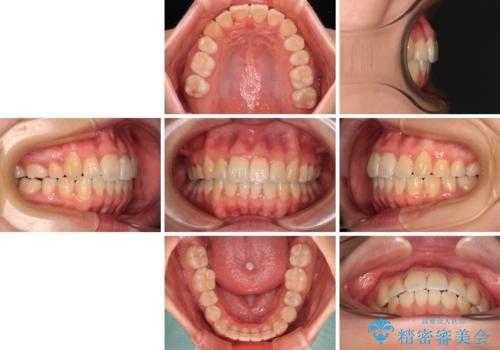

【モニター】八重歯を片側の抜歯矯正で治す メタルブラケット装置

お仕事の予定を調整しやすく、平日の昼の時間帯に通院可能であったので、非常にスムーズに治療を進めることができ、1年半で無事に治療を終えることができました。